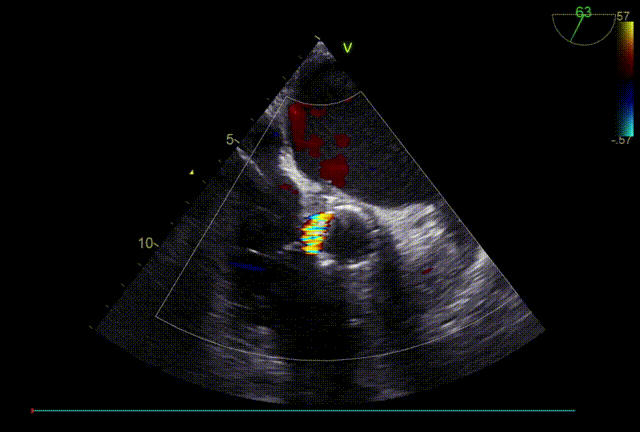

TTE